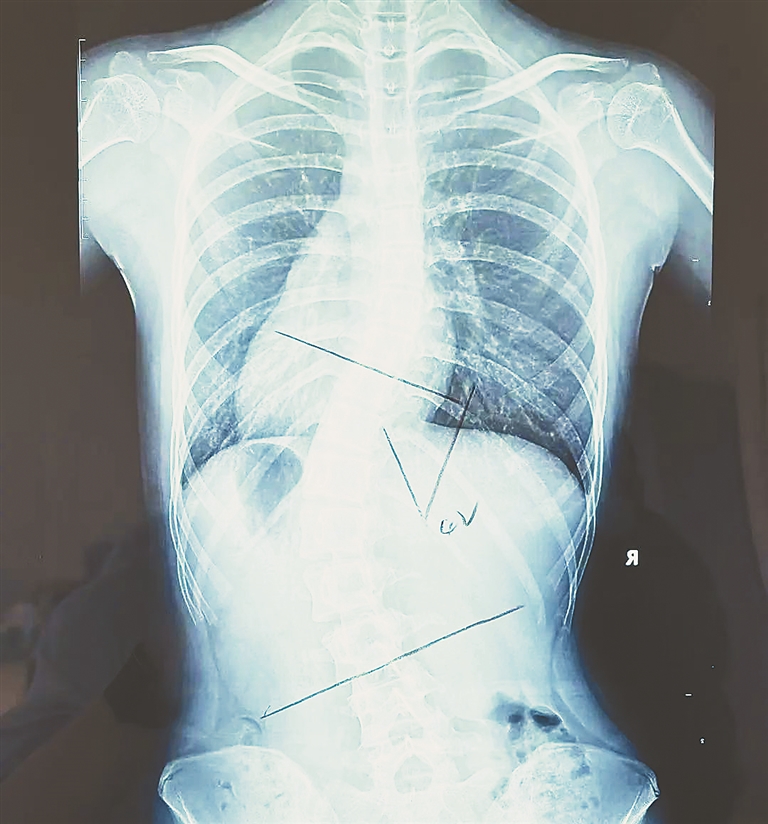

“就诊时,小贝的脊柱侧弯主弯度cobb角已达42度,弯曲很严重,接近手术边缘,当时家属决定进行保守治疗。”据脊柱侧弯中心康复治疗师孙晓蕾介绍,脊柱侧弯中心医生团队为其采取定制支具以及个性化脊柱侧凸特定运动疗法等方式进行康复治疗,经过8个月细心诊治,小贝在去除支具24小时后,弯度从42度降低至21度。